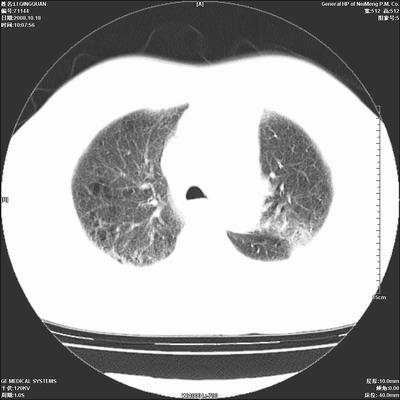

以下是引用ybing在2008-10-19 12:58:00的发言:[br]左肺上叶阻塞性炎症-建议支气管镜进一步检查除外中央型肺癌

以下是引用duguo在2008-10-19 13:59:00的发言:[br]左肺上叶支气管狭窄,首先考虑中心型肺癌伴阻塞性肺炎\\肺不张.

以下是引用随光逐影在2008-10-19 14:31:00的发言:[br]考虑左肺中央型肺癌并左肺上叶阻塞性肺炎,肺不张。